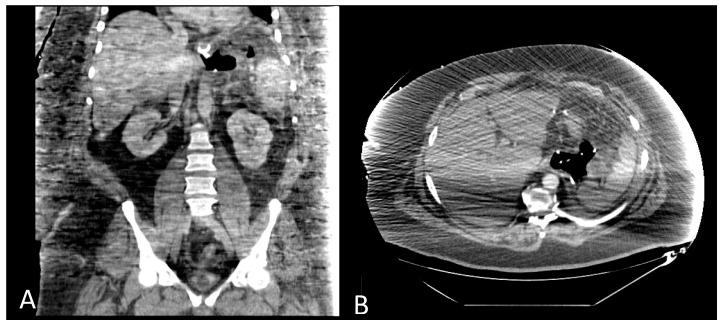

Post-sleeve gastrectomy fistulas are a rare but possibly severe life-threatening complication. Besides early reoperation and drainage, endoscopy is the main treatment option. According to the clinical setting, endoscopic treatment options comprise stent or clip placement. New endoscopic therapies have recently gained attention, including endoscopic vacuum therapy, VacStent therapy, endoscopic internal drainage with pigtail stents, endoscopic suturing and stem cell injection. In this narrative review, we shed light on recent literature, developments, indications and contraindications of these treatments. Intragastric gastric band migration is a rare complication after gastric band positioning. Reoperation can sometimes be difficult, especially when a gastric band has already migrated far into the stomach. Endoscopic retrieval can be a valid, non-invasive therapeutic solution. We reviewed the current literature on this matter.

袖状胃切除术后瘘是一种罕见但可能严重危及生命的并发症。除了早期再次手术和引流外,内镜检查是主要的治疗选择。根据临床情况,内镜治疗方法包括放置支架或夹子。最近,新的内镜治疗方法受到关注,包括内镜下负压治疗、VacStent治疗、猪尾支架内镜内引流、内镜缝合和干细胞注射。在这篇叙述性综述中,我们阐明了这些治疗方法的最新文献、进展、适应证和禁忌证。胃内胃束带移位是胃束带放置术后的一种罕见并发症。再次手术有时可能很困难,尤其是当胃束带已经深入胃内时。内镜取出可能是一种有效的非侵入性治疗解决方案。我们回顾了关于此事的当前文献。